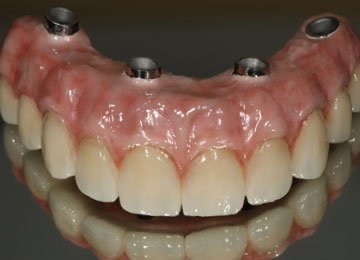

Лучшим способом решить проблемы беззубой верхней или нижней челюсти является имплантация зубов «All-on-4», при которой на одном ряду устанавливают 4 импланта, предназначенных на роль опоры, а затем на них крепят протез, состоящий из 12 коронок.

Структура протеза по методике All-on-4

В искусственном зубе есть три структурных элемента – искусственный корень, абатмент, коронка. При одномоментной имплантации, когда зуб устанавливают в лунку только что удаленного зуба, промежуточная часть может отсутствовать.

Протезирование на четырех имплантах предусматривает использование временных и постоянных протезов, при этом облегченные временные протезы выполняются из ортопедической пластмассы, а для постоянных протезов используют диоксид циркония, металлокерамику, керамику. Мы используем препараты и материалы мировых брендов, клиника работает только с имплантами: Straumann, Osstem и Ankylos, прошедших проверку и зарекомендовавших себя как лучшие мировые производители. Каждая из этих торговых марок постоянно расширяет ассортимент продукции и дает возможность подбирать материалы для любых клинических случаев.